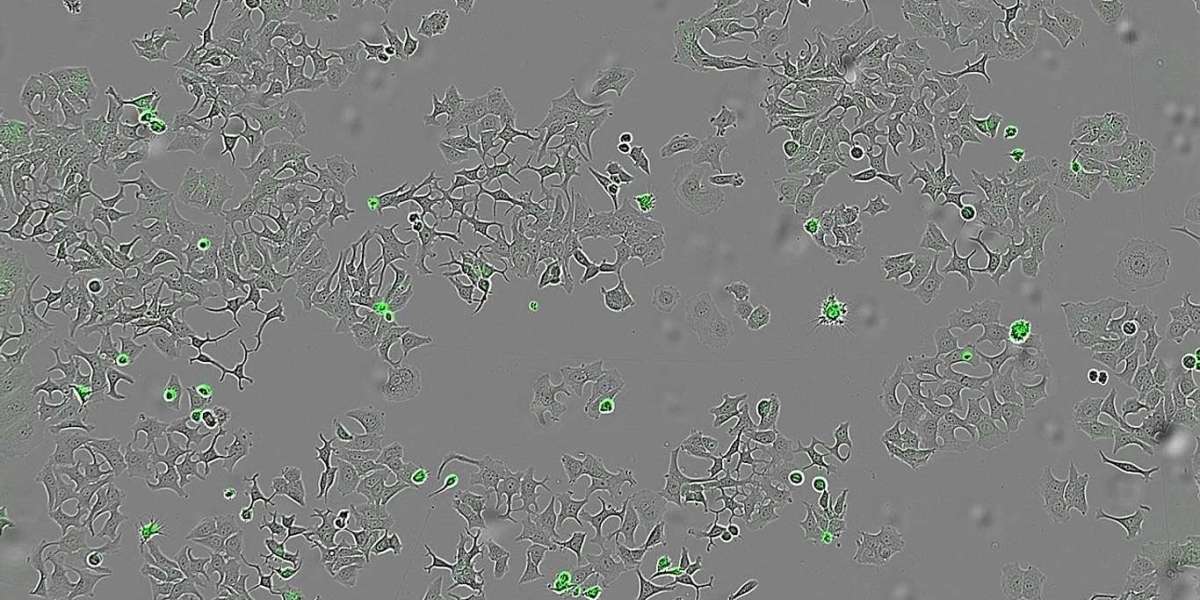

Published in the journal Cell Death Discovery, the research focused on the effects of HapA on breast, colon, and pancreatic tumor cells in laboratory settings. In each case, the presence of HapA significantly reduced cancer cell survival and proliferation.

What makes HapA especially promising is its precision. In experiments, researchers used mutant strains of Vibrio cholerae that lacked HapA, as well as genetically modified strains designed to produce only this protein. The cancer-killing effect was observed only in the presence of HapA — a strong indicator of its unique role.

To evaluate its broader effectiveness, scientists also exposed cancer cells to liquid extracts containing all proteins secreted by the bacteria. The goal was to assess whether HapA could maintain its tumor-killing ability across different cancer types. According to Hurtado, "We wanted to see if human cells of different tumour types were still alive and could multiply after being in contact with these bacterial substances, particularly with the HapA protein."

The results were consistent: HapA reduced the ability of tumor cells to survive and multiply, further validating its therapeutic potential.